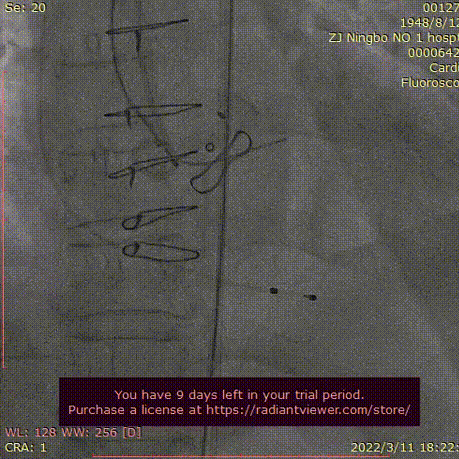

导丝跨瓣